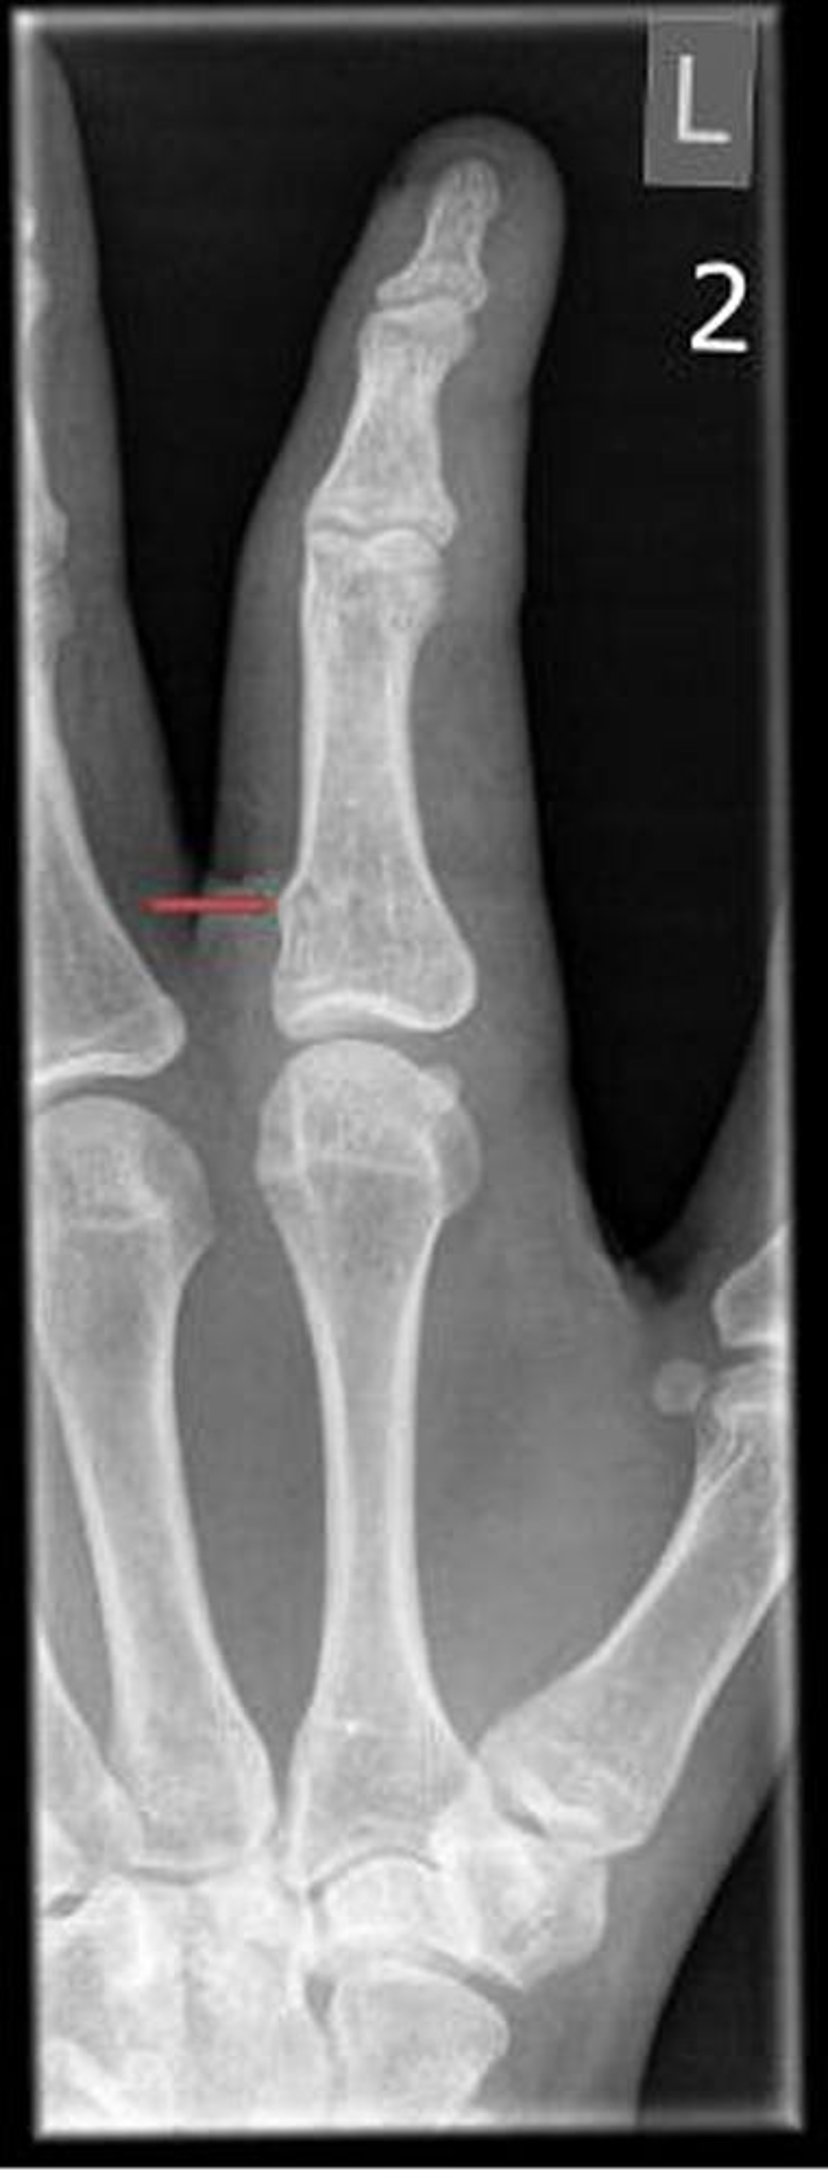

Fracture en tore du doigt

Les fractures en tore ne sont visibles que sous la forme d'irrégularités subtiles de la corticale osseuse.

PHOTOSTOCK-ISRAEL/SCIENCE PHOTO LIBRARY